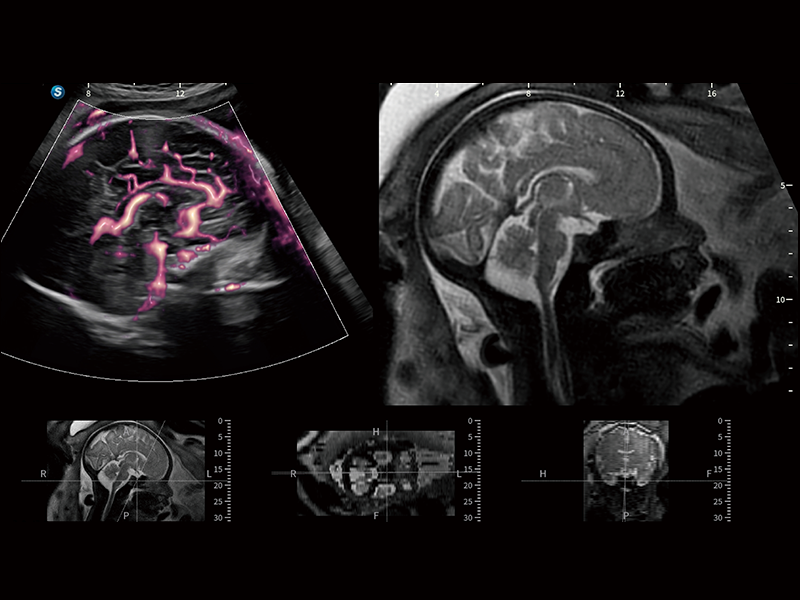

豐富的血流動(dòng)力學(xué)檢測(cè)技術(shù),可在不同醫(yī)療場(chǎng)景中高效捕捉血流信號(hào),助力臨床診療。

在傳統(tǒng)血流的基礎(chǔ)上優(yōu)化掃查和算法策略,能夠更好的抑制組織信息,提煉紅細(xì)胞運(yùn)動(dòng)信息,得到更高幀頻,高靈敏度和分辨率的血流信號(hào),還原更真實(shí)的血流動(dòng)力學(xué)。

通過(guò)光照模型,使二維血流顯示出立體的效果,增加血流的敏感性、成束性,減少外溢??梢院推渌煌难骷夹g(shù)聯(lián)合使用,融合不同技術(shù)的優(yōu)勢(shì)。輕松應(yīng)對(duì)微小血管,增強(qiáng)血流的立體效果,提升視覺(jué)敏感性。

通過(guò)創(chuàng)新的Matrix E自適應(yīng)濾波算法,能有效濾除軟組織和噪聲信號(hào),最大限度保留超低速微細(xì)血流的信號(hào);結(jié)合超長(zhǎng)時(shí)間域算法,極大提升細(xì)微血流的敏感性和空間分辨率,更真實(shí)的反應(yīng)組織、包塊的血流灌注情況。